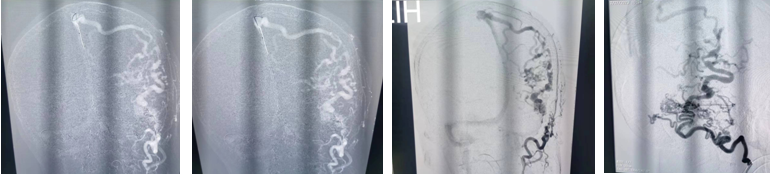

手术当天,在麻醉科手术室全力配合下手术顺利开展。王沛医师先进行血管显影,栓塞。术中发现枕动脉有几处分支迂曲,难以通过,进行部分栓塞后转行开颅。开颅设计跨横窦切口,充分暴露横窦上下3cm硬脑膜。幕上剪开硬膜后暴露瘘口及引流静脉。仔细辨别后予以双极电凝烧闭靠近横窦引流静脉及瘘口。幕下烧灼引流静脉,显微剪断除细小引流静脉。整个手术过程顺利,出血控制良好。术毕行DSA检查,杂论血管团消失,脑膜动静脉瘘消失,术后安返病房。目前患者已经清醒,四肢活动正常。